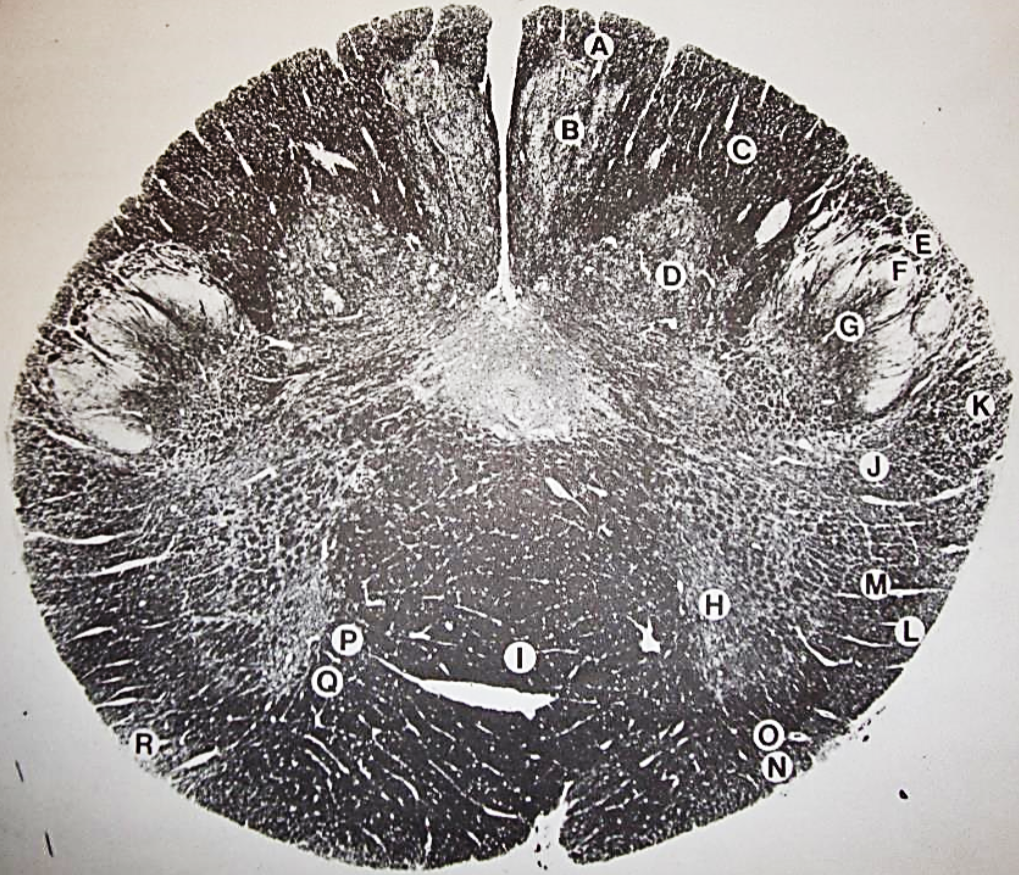

A

Lateral Cuneate nucleus

B

dorsal external arcuate fibers

C + D collectively

vestibular nuclei

C + D collectively

vestibular nuclei

E

dorsal motor nucleus of vagus nerve

F

solitary fasciculus

G

solitary nucleus

H

nucleus ambiguous

I

fascicles of glossopharyngeal nerve

J

hypoglossal nucleus

K

fascicles of hypoglossal nerve

L

dorsal longitudinal fasciculus

M

central tegmental tract

N

inferior olivary nucleus

R

inferior cerebellar peduncle

S

spinal trigeminal tract

T

spinal trigeminal nucleus

U

ventral trigeminothalamic tract

V

pyramidal (corticospinal) tract

W

rubrospinal tract

X

anterior spinocerebellar tract

Y

spinal lemniscus

Z

medial longitudinal fasciculus

a

tectospinal tract

b

medial lemniscus

c

vagus nerve

d

inferior salivatory nucleus